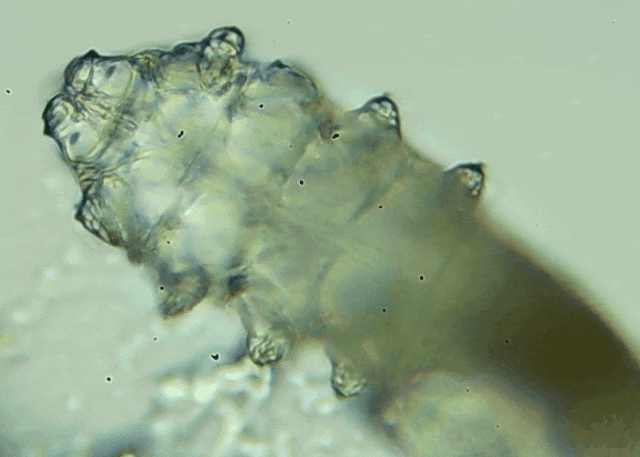

我只是眼睛癢,結(jié)果醫(yī)生說我睫毛里有80只蟲?這不是恐怖片,而是真實的病例:武漢一13歲男孩,右眼9根睫毛里檢出39只螨蟲,左眼9根里檢出47只。 而且這不是極端個案,廈門眼科中...

眼瞼位于眼球前面,分為上下眼瞼,而睫毛、一些腺體的開口和淚小點都在眼瞼邊緣,也就是瞼緣上。蠕形螨是一種寄生于毛孔、腺管和瞼緣上的螨蟲,因為體型微小,肉眼無法察覺。...[詳細(xì)]